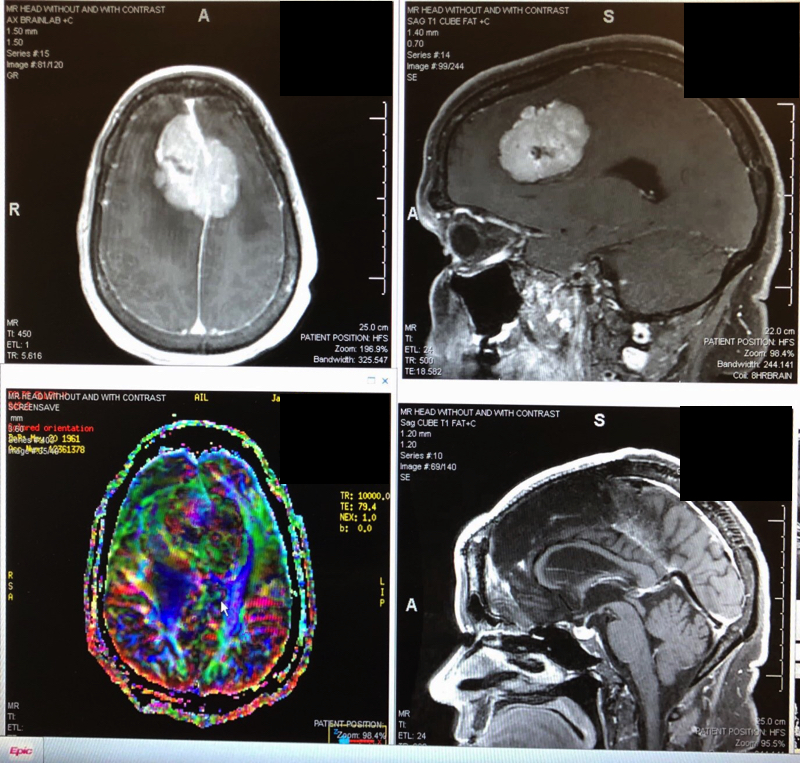

Top and bottom left: brain tumor before surgery. Bottom right: after stereotactic radiosurgery.